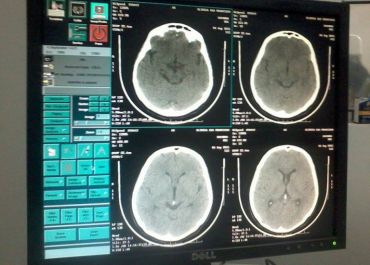

Clinica São Francisco implanta Tomografia Computadorizada Helicoidal em Campo Maior

Com imagens de alta definição e capacidade de cortes cada vez menores (até 1 mm) e reconstrução de imagens, a Cliníca chega a um novo patamar de evolução.